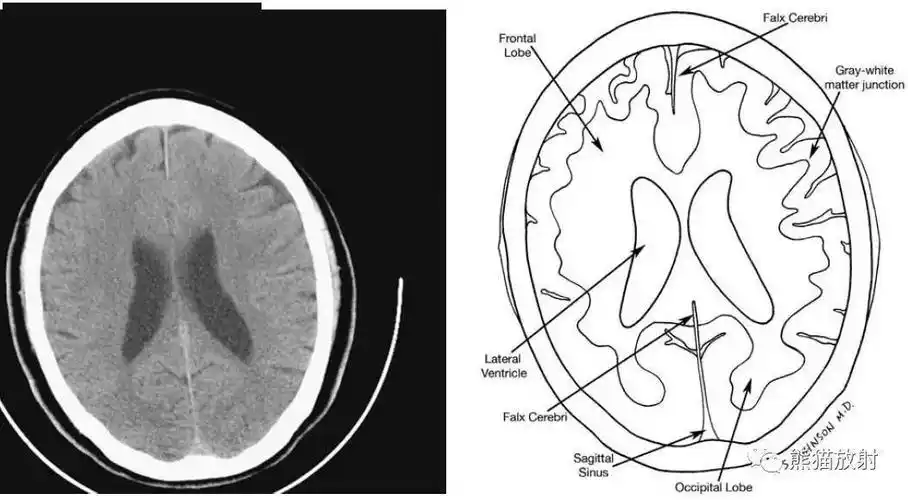

颅脑ct的正常解剖